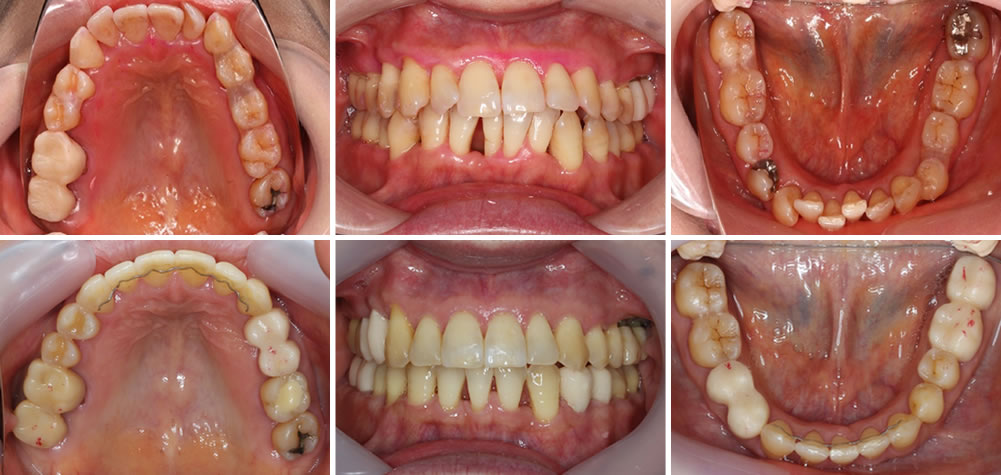

10代男性 治療期間:36ヶ月 抜歯:上下左右1本ずつ 治療費770,000円

大学生の男性です。上下の前歯のデコボコが気になるとのことで来院されました。デコボコの度合いが重度であったため、治療方針として上下左右の歯を1本ずつ抜歯して矯正治療を行いました。治療期間が長くなってしまいましたが、歯磨きが簡単になったと言って下さり、咬み合わせにも大変満足して頂きました。

【リスク】

・歯の移動の際に痛みを感じる場合がある。

・矯正治療後は、保定装置を装着しなければ歯が後戻りする場合があります。 -